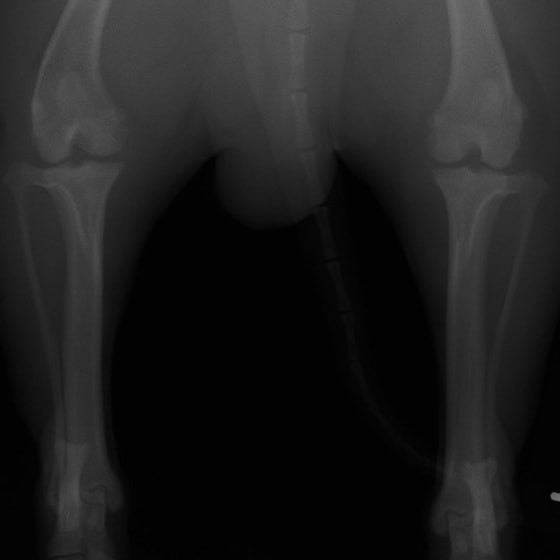

左後肢の挙上を主訴に来院されました。触診にて両関節の前方引き出し兆候、両膝蓋骨の内方脱臼を認めました。関節液検査より免疫介在性多発性関節炎は否定的でした。レントゲン検査にてfat pad signを伴う関節炎が認められたことから、前十字靭帯断裂と膝蓋骨内方脱臼(左GradeⅢ 右GradeⅢ〜IV)併発と診断し、手術を行いました。

術前正面像

術前のTPAは左後肢33.1°右後肢26.8°でしたがTPLO実施により左後肢5.5°右後肢12°に矯正されました。